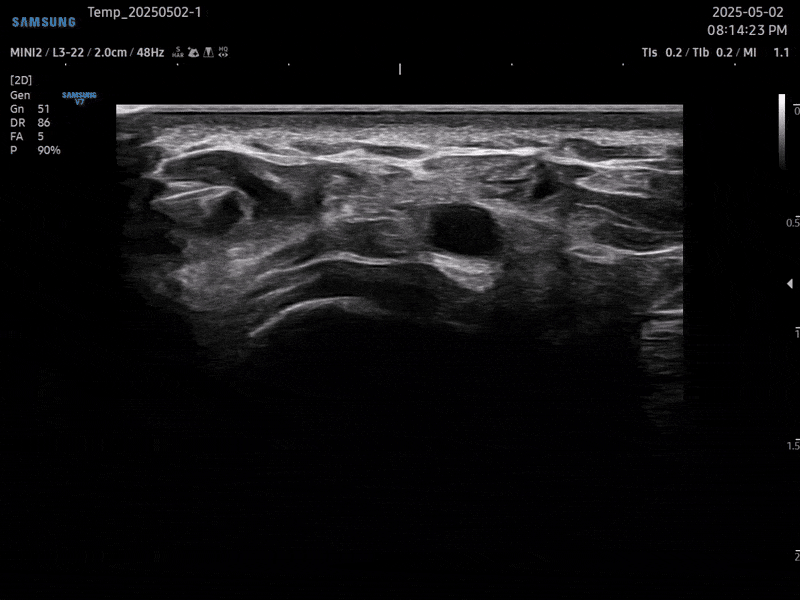

초음파 검사를 통해

손가락 골관절염 통증의 직접적인

원인을 확인할 수 있습니다.

연골, 활막, 건초의 상태를 진단하고

정확한 부위를 치료하여 손가락 관절의

근본적인 통증을 해결합니다.